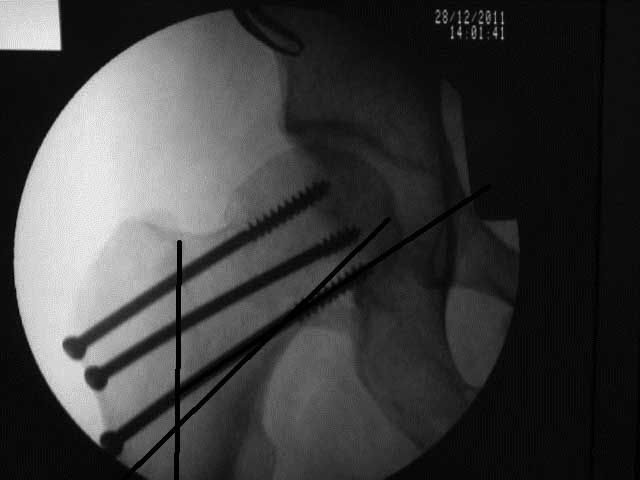

[Ortho] перелом шейки бедра

Или всё таки красивее было бы вот так? И при нагрузках динамизация по винту?